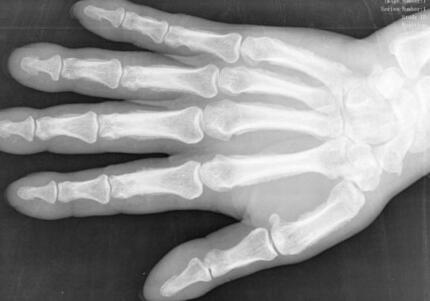

常规X线平片检查时,可以发现掌指关节和近侧指间关节的关节下有囊肿形成、骨侵蚀、关节间隙狭窄和骨赘形成。在腕骨和下尺桡关节亦有囊肿形成和侵蚀。少数远侧指间关节也可有变化。关节下囊肿最早出现,通常位于关节近侧,常见的是掌骨头部的关节下区有直径1~3mm的圆形或卵圆形的小囊肿,周边有界限清晰的硬化区。随后出现关节间隙狭窄和骨赘形成。关节间隙狭窄不均匀,在关节受侵蚀处最为明显。但关节间隙狭窄并不一定与囊肿形成相一致,有时可有数个关节下囊肿形成而无关节间隙狭窄;也可以有明显的关节间隙狭窄而无囊肿形成。骨赘形成一般是关节严重受累的表现,但并不一定伴有明显的关节间隙狭窄。腕骨内可有边界清晰的囊肿,其直径5~6mm,常为多发性;同一骨内也可有2~3个囊肿,常见于头状骨、钩骨、舟骨和月骨。

部分患者的远端尺桡关节和尺骨远端也可能有改变。在尺骨远端和茎突处可有数处囊肿和骨侵蚀。少数病例可在该关节的桡侧出现囊肿,甚至在三角韧带处显示混浊阴影。